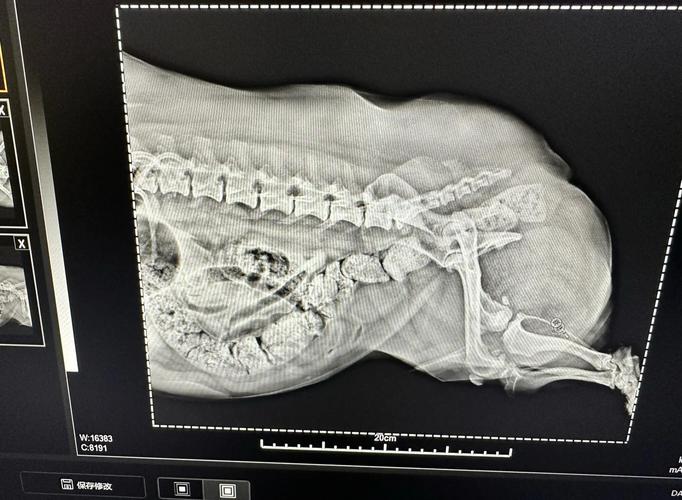

狗狗吃骨头不消化的症状主要包括便秘、食道梗塞、食道划伤、感染寄生虫以及牙齿受损。 便秘狗狗吃了过多的骨头,尤其是硬骨头,可能会导致大便干燥,长期如此就可能引发便秘。便秘会使狗狗感到非常痛苦,宿便长时间留在体内会影响其健康,甚至导致肠胃功能失调。

〖Three〗、一方面,坚硬的牛骨头可能会损伤狗狗的消化系统。狗狗的消化道相对较短,胃酸含量较高,肠壁厚、吸收能力强,适合消化肉食,但并不擅长处理坚硬的骨头。狗狗在啃咬过程中,骨头碎片可能会划伤口腔、食道或胃肠道,导致出血、感染甚至穿孔。